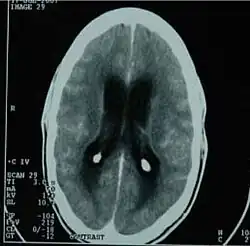

CT scan showing tuberculous meningitis

Diagnostic methodBlood culture, CT scan[2]